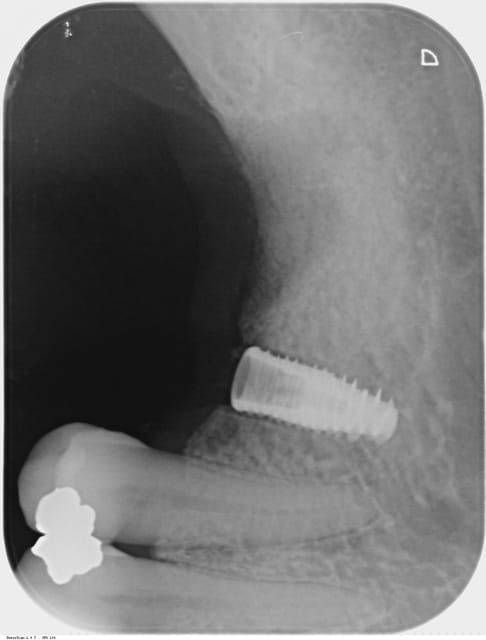

On dirait sur la premier radio que tu as sur-foré par rapport aux diametre de l'implant .

Tu aurais pas passé un foret supplémentaire ?

edit : je viens de relire , tu as changé d'axe en milieu d'intervention .

Ta stabilité primaire était bonne ?

C'est un implant distal, aucune protection en postérieur, perso je pense qu on ne prend pas assez en considération la puissance de la langue et des joues.

ta bague de cicatrisation est haute et large ce qui permet de forces latérales considérables, et tu dis toi même que tu "n’étais" peut-être pas satisfait de ta stabilisation primaire!

Je partage cet avis au sujet de la vis de cicatrisation, je la trouve trop haute (grand effet de levier ) et trop large ( grand plateau occlusal avec lequel le patient mastique) .

On devine aussi l'alvéole de la 7 sur la radio : l'extraction n'est-elle pas trop récente ?